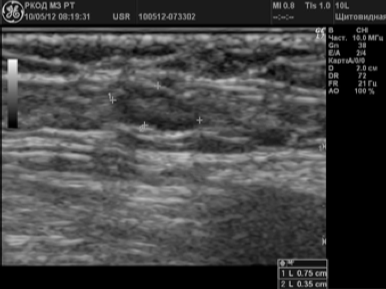

Criterii de ultrasunete a stării normale (nemodificat) a ganglionilor limfatici au fost considerate [3-5] (Figura 1.):

- în principal, de formă ovală, alungită;

- de frontieră - contururi clare - netede;

- raportul P / PP> 2,0;

- Dimensiunea de-a lungul axei lungi - nu mai mult de 1,5 cm;

- prezența diferențierii în cortexul și poarta (în mod normal, situate la periferia părții hypoechoic LU - scoarță, în timp ce în partea centrală - partea hiperecogen - porți).